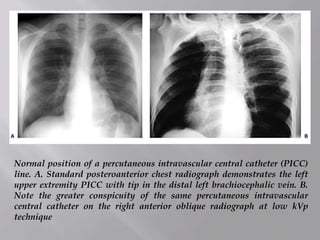

Normal position of a percutaneous intravascular central catheter (PICC)

line. A. Standard posteroanterior chest radiograph demonstrates the left

upper extremity PICC with tip in the distal left brachiocephalic vein. B.

Note the greater conspicuity of the same percutaneous intravascular

central catheter on the right anterior oblique radiograph at low kVp

technique